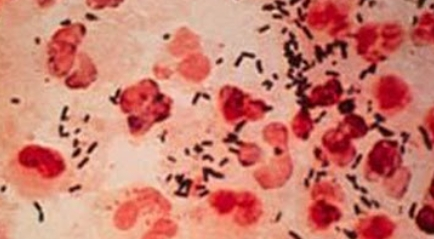

임균 감염증, 일명 임질은 성병 중 하나로, Neisseria gonorrhoeae 세균에 의해 발생합니다. 이 병원균은 인체의 점막을 감염시켜 성기, 항문, 목, 눈 등에 다양한 증상을 유발할 수 있습니다.

임균 감염증은 Neisseria gonorrhoeae라는 균에 의해 발생합니다. 이 균은 성적 접촉을 통해 전달되며,

특히 미성년자, 젊은 성인, 그리고 성 파트너가 다수인 개인에게서 더 자주 발생하는 경향이 있습니다.